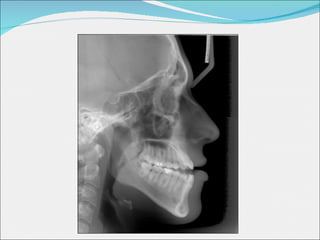

Estudi de diferents casos Problema estètic Sistema Damon Mecànica convencional Problema funcional Sistema Damon Mecànica convencional

PROBLEMA FUNCIONAL: SISTEMA DAMON

Inicials Finals